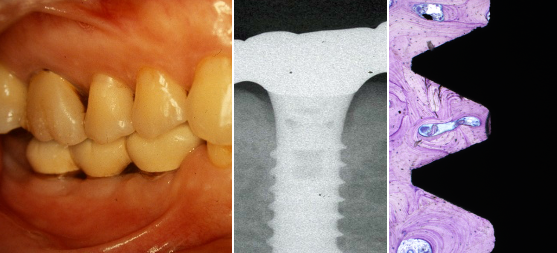

< インプラントのオッセオインテグレーション >

< インプラント周囲炎 >